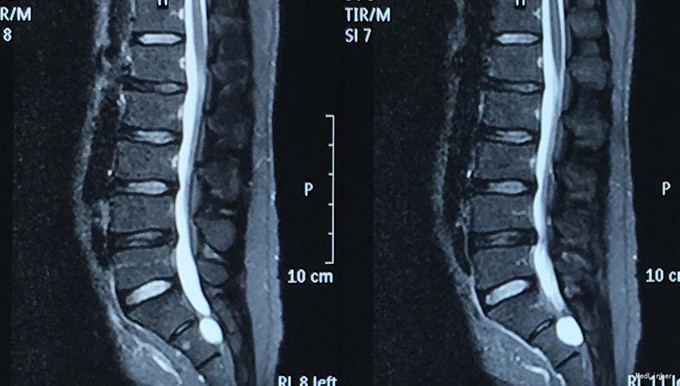

查体:脊柱生理弯曲存在,腰椎活动受限,L4/L5,L5/S1棘突压痛叩痛,叩击痛。左侧直腿抬高试验(+),约35°,加强试验(+),约30°。左下肢外侧皮肤感觉稍减退,右侧正常。双侧髂腰肌、股四头肌肌力Ⅴ级、左侧胫前肌、踇背伸肌肌力Ⅳ级,腹壁反射、肛门反射正常,两侧膝正常,双侧踝反射对称减弱。双侧Babinski征(-),双侧皮温及色泽正常,双侧足背动脉搏动良好。 辅助检查:腰椎磁共振检查显示:腰4/5椎间盘向左后方突出,压迫左侧神经根。骶管骶4水平发现一大小约2*3*3大小的囊肿。

诊断:1.腰4/5椎间盘突出症;2.骶管囊肿; 治疗:给予行左侧腰4/5椎板间开窗髓核摘除术。术后左腰臀部疼痛缓解明显,瞩其定期复查腰椎核磁共振。